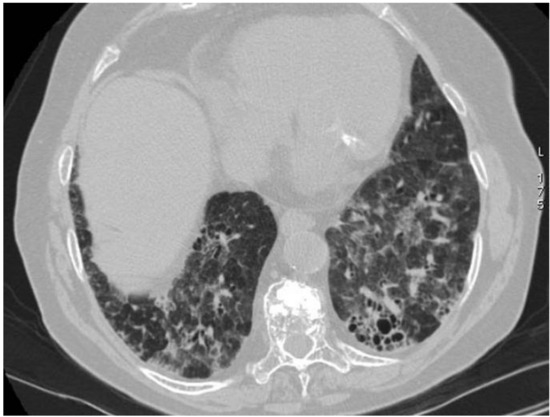

2.5. Eosinophilic Granulomatosis with Polyangiitis (EGPA-Churg-Strauss)

| Vasculitis | HRCT Features |

|---|---|

| EGPA | Migrant GGOs, transient consolidation, irregular bronchial wall thickening, small nodules with peribronchial and centrilobular distribution, pleural effusion. |